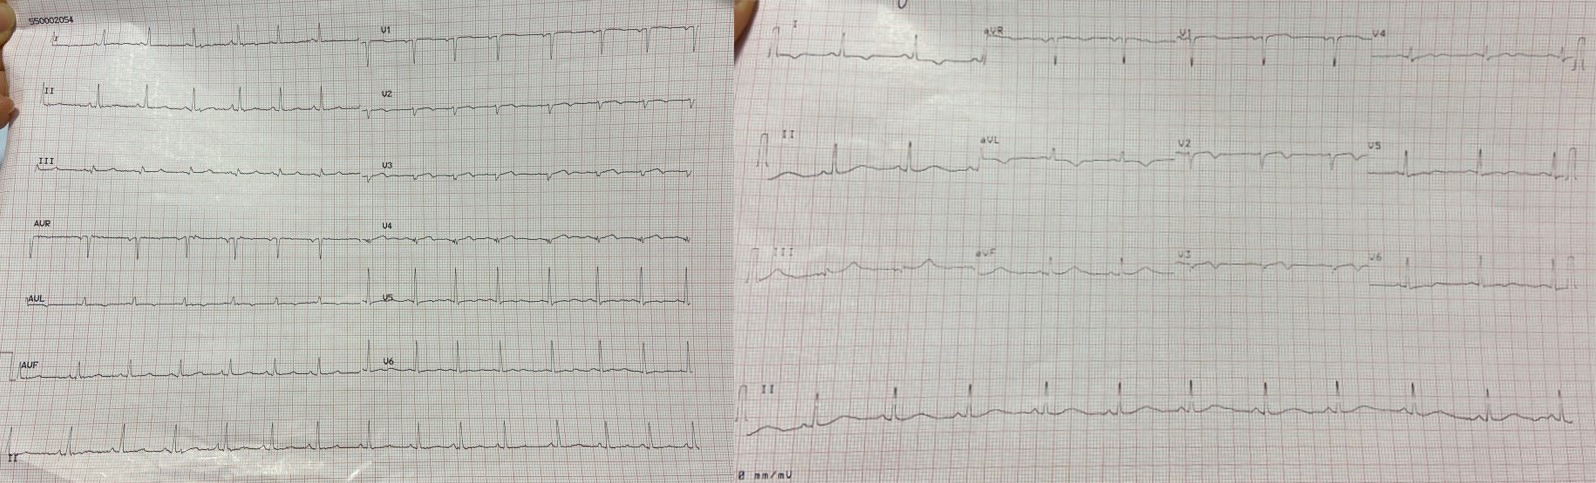

During the patient’s hospital stay, she experienced several episodes of acute chest pain. A re-evaluation of the ECG during these episodes revealed isodiphasic T waves in leads V2 and V3 (Fig. 7).

Fig. 7.

Fig. 7.A re-evaluation of the ECG during episodes of acute chest pain revealed isodiphasic T waves in leads V2 and V3. ECG, electrocardiogram.

When the ECG was recorded at rest, without symptoms, it displayed negative T waves in the extended-anterior region (Fig. 8).

Fig. 8.

Fig. 8.ECG at rest, in the absence of symptoms, displays negative T waves in the extended-anterior region. ECG, electrocardiogram.